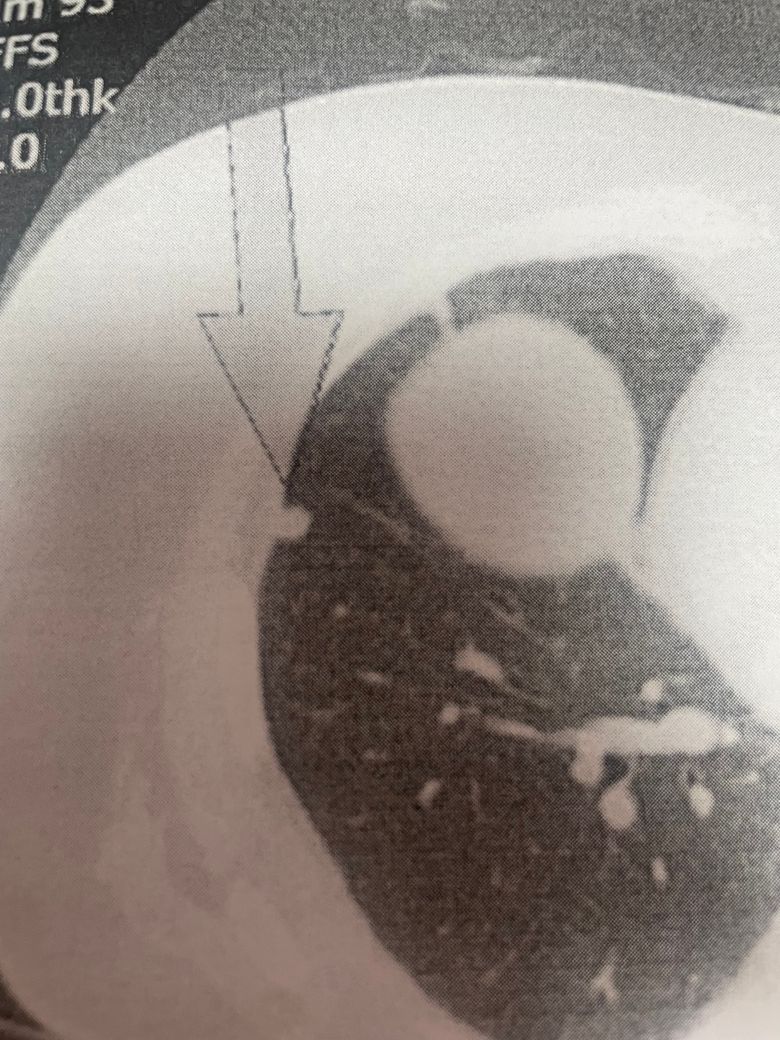

71세이고 여성입니다 22년에는 결절이 없었고 23년 3월에 코로나를 세게 걸렸고 23년 6월에 폐결정 8미리 rll 바깥쪽에 있었거 그해 9월에 검사 다시 해보니 크기 변화 없었고 24년 9월에 다시 찍어보니 2미리가 자라서 10미리가 되었습니다 위험한건가요??일단 삼개월뒤에 다시 찍기로 했습니다 모양은 원형인거 같습니다